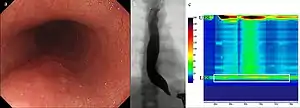

Endoscopia

Para descartar «complicaciones» se suele acudir a una endoscopia digestiva alta.

Permite confirmar el carácter funcional del afinamiento terminal del esófago, al vencerlo mediante una suave presión del endoscopio. Esto no ocurre cuando la estrechez es orgánica, por inflamación o neoplasia.

La endoscopía es necesaria para descartar otras patologías, antes de cualquier tratamiento.

Manometría esofágica

El diagnóstico es confirmado por medio de una Manometría esofágica de alta resolución, que mide las presiones del esófago mediante una sonda nasoesofágica y permite comparar las presiones en situación basal y durante la deglución.[8] Se inserta un tubo delgado a través de la nariz, y se le instruye al paciente a deglutir varias veces. La sonda mide las contracciones musculares en diferentes partes del esófago durante el acto de la deglución. La manometría revela la falla del EEI para relajarse con cada deglución y la falta de peristaltismo funcional del músculo liso en el esófago.